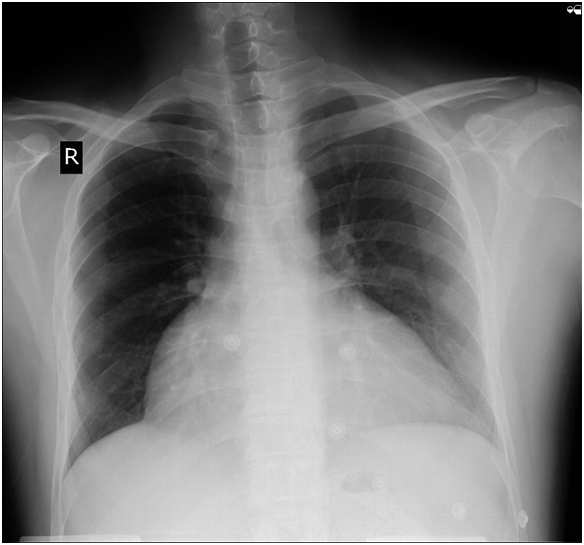

27years old male patient admitted to our outpatient clinic with progressive, pleuritic chestpain unrelated to exertion for a month with no significant medical history. The patient was diagnosed with acute pericarditis at an center and receiving ibuprofen and colchium treatment for three weeks. There was no pathological finding on cardiacaus cultation, blood pressure was 110/80mmHg, heart rate was 110bpm. Electrocardiography showed sinustachicardia and minimal ST segment elevation in all leads. There was a slight cardiomegaly in chest X-ray (Figure 1). Cardiac markers and inflammatory marker were elevated; troponin-I 1112ng/L (0-100), CK748 U/L (0-190), CK-MB 95 U/L(3-25), ESR 65, CRP 75 was detected. Transthorasic echocardiography revealed a 45x60 mm of cavitary mass compressing the right atrial free wall along with pericardial effusion (Figure 2); which was the only location of pericardial effusion in his previous examination a month ago. The patient was admitted to CCU. An aneursym 100x70x60mm in diameter, originating from right coronary artery extending to right atriallateral wall border and compressing externally, which contains thrombus material in its cavity was detected in cardiac computed tomography (CT) (Figure 3). Coronary angiography revealed a giant aneurysm communicated with RCA (Figure 4) without any abnormalty on left coronary arteries. The patient was given to emergency surgery because of the risk of pericardial tamponade. Aneurysmectomy was done and the remained cavity was closed primarily. Pathological examination was reported as polymorpho nuclear leukocyte and mononuclear inflammatory cell infiltration without elastic fibers and a pseudoaneursym of the coronary artery. The patient was discharged without any complication.

Figure 3 Right coronary artery aneurysm and the thrombus material extending to the right atrial lateral wall. (White arrow).